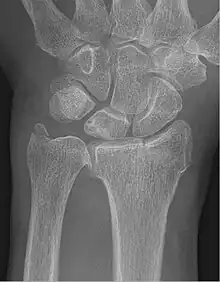

| Fracture of the radial styloid process with the fracture line extending into the intraarticular surface | |

Chauffeur's fracture, also known as Hutchinson fracture, is a type of intraarticular oblique fracture of the radial styloid process in the forearm.[1] The injury is typically caused by compression of the scaphoid bone of the hand against the styloid process of the distal radius. It can be caused by falling onto an outstretched hand. Treatment is often open reduction and internal fixation, which is surgical realignment of the bone fragments and fixation with pins, screws, or plates.